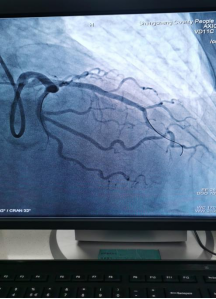

日前,商城县人民医院胸痛中心群里在半个小时内先后报告了两例来自李集乡的急性心梗患者,一场与时间赛跑,与死神博弈的生死急救快速拉开了帷幕!

急诊PCI对医院的硬件、人员配备等要求极高,能否开展急诊PCI目前已成为心血管领域彰显医院整体诊疗水平的标志。一台台成功的手术、一个个因救治及时而重获新生的患者,无不体现着我院胸痛中心日臻成熟的精确诊疗技术!也显示出我院在介入治疗领域已具备较强的综合实力。不论白昼还是黑夜、疾风或是暴雨,胸痛中心的电话就是命令!时间就是生命,时间就是心肌,胸痛中心团队始终秉持着生命至上、人民至上的理念,他们每天与时间赛跑,与死神搏斗!节省的每一分每一秒都在为急性心肌梗死患者争取生的希望,力求实现胸痛救治从急救到预防,从急病到慢病的延伸,随时待命为大别山区广大心血管疾病患者保“心”护航!